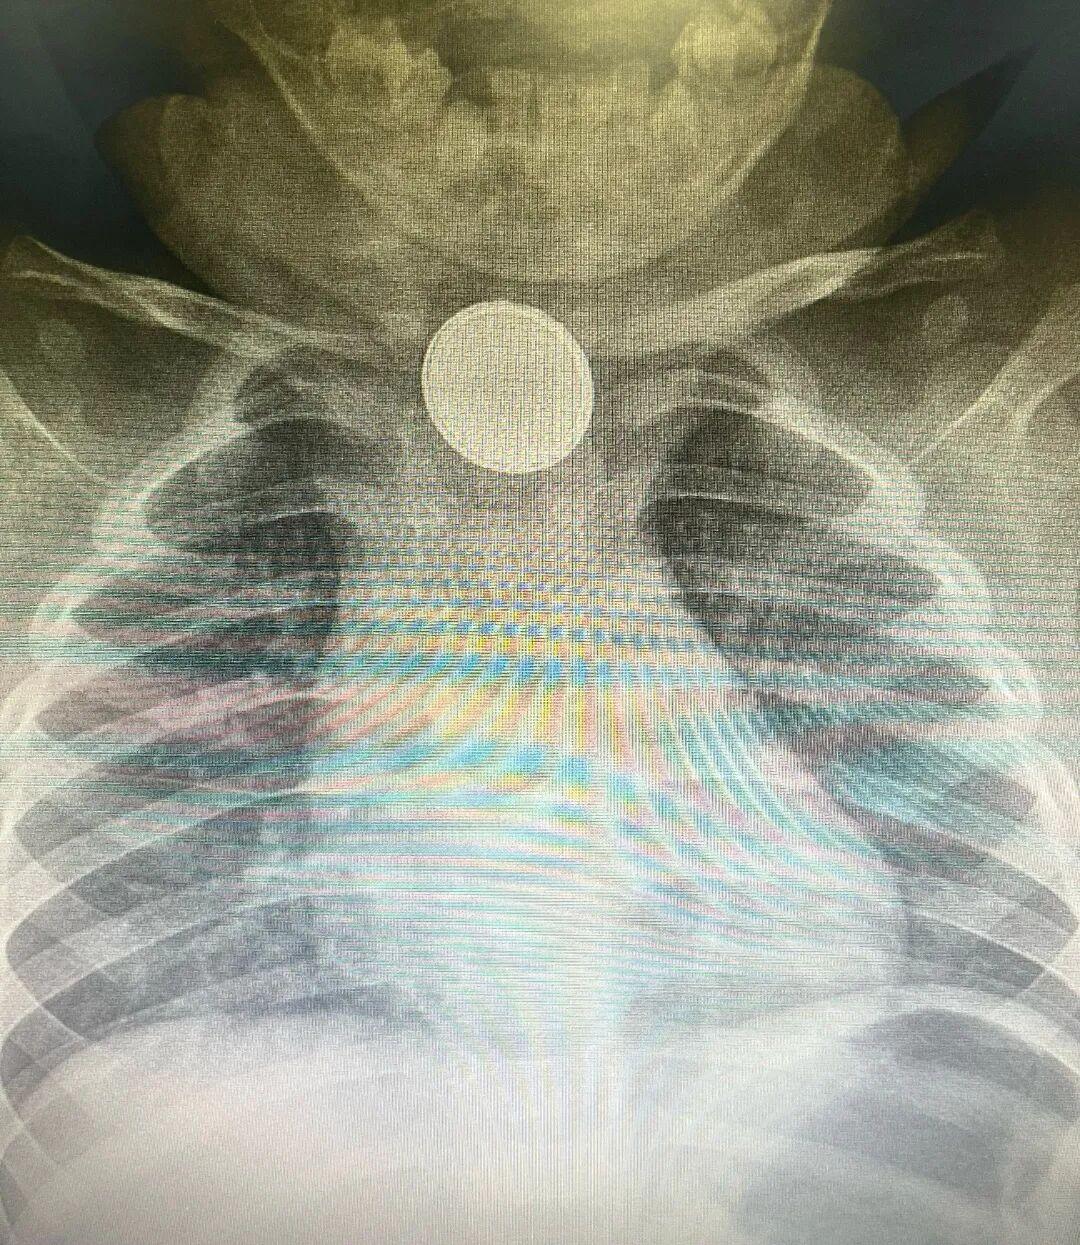

急诊医师凭借丰富经验,初步判断是消化道异物,当即安排检查。X线片很快给出答案——食管处可见出现一个类圆形高密度影。

类圆形高密度影